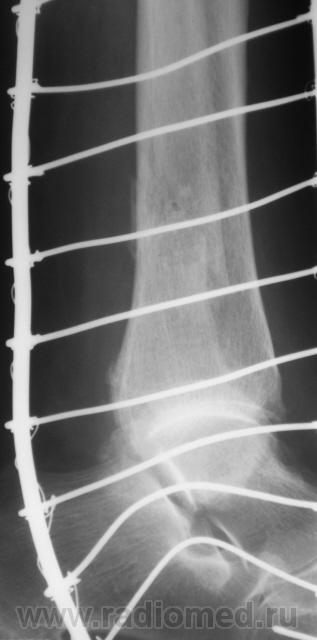

Перелом наружной и задней лодыжек. Подвывих в голеностопном суставе кнутри. Подвывих в тараннопяточном суставе. Разрыв дистального межберцового сочленения.

Переломы латеральной и медиальной лодыжек, пронационный подвывих в голеностопном суставе, латеральный подвывих в таранно-пяточном, разрыв межберцового синдесмоза.

Almo правильно задал вопрос, это касается терминологии. Про вывих стопы говорят, когда имеется вывих в г/ст суставе, а подтаранный N. Если имеется вывих в голенностопе и в подтаранном в противоположные стороны, т.е. смещается только таранная кость, говорят о вывихе таранной кости. Данный случай относится именно к последнему.